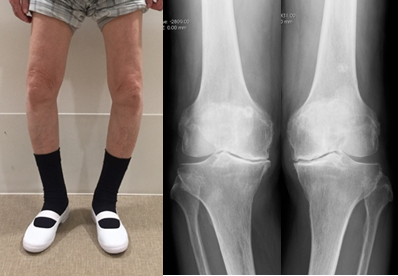

両側O脚変形、両側同時TKA